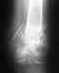

Нужен Ваш совет !!9 октября 2009 произошел травматический вывих левого надколенника.

Вывих был повторный( первый - 3 года назад). После этого я вроде восстановился и начал активно заниматься спортом. Вывих произошел на ровном месте, в спорт.зале я споткнулся и вот результат. В больнице сделали 2 пункции : удалили около 200 мл.крови. Проделали процедуры : магнит, ультразвук и электростимуляцию. Врачи настоятельно советуют делать операцию, сказали, что до лета можно потерпеть, т.к. я - студент медицинского вуза. И все... Может вы посоветуете, какие препараты можно принимать для восстановления связок, какие упражнения делать, может нужно сделать УЗИ капс.-связ.аппарата, может вы предложите программу реабилитации и есть ли альтернатива операции?